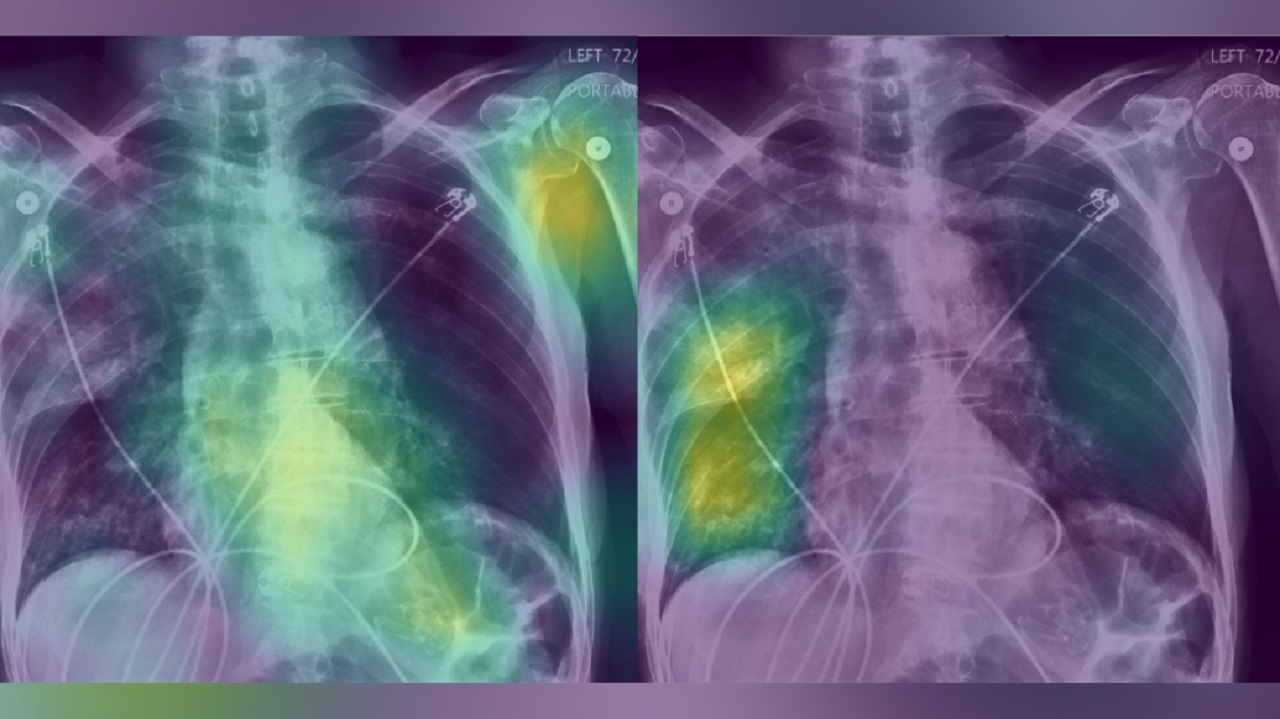

Для половины участников, которые были случайным образом выбраны для получения обоснований, предоставлялась тепловая карта, или визуальное представление, того, куда модель ИИ смотрела на рентгенограмме грудной клетки, что и послужило основанием для постановки диагноза.